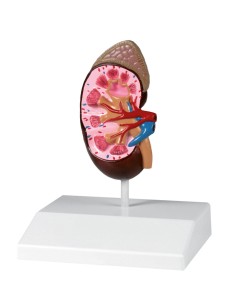

Modèle anatomique de néphron avec vaisseaux sanguins, agrandi 120 fois k10/1